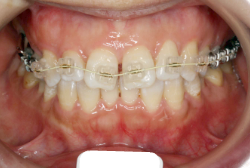

成長発育期の叢生症例・非抜歯治療

今回は「歯並びの凸凹を治したい」という主訴で来院したケースです。診断の結果、「成長発育期の叢生」と判明しました。叢生とは歯並びの凸凹のことですが、この方の場合は上顎が少々重症で、上の犬歯が外側へ飛び出し、いわゆる「八重歯」という状態でした。凸凹の解消のためには永久歯を抜歯して隙間を作って残った歯をきれいに配列する方法(抜歯法)と、歯列を拡大して配列する方法(非抜歯法)の2種類があります。歯列の拡大にはさらに2つの方法が有り、横方向へ拡大する場合と、臼歯を後方に移動させて拡大する方法があります。今回の症例のようなケースでは、横方向へ拡大してもあまり効果的ではなく、後方への移動が最適です。上の臼歯を後方へ移動させるために、今回はヘッドギヤという取り外し式の装置を、夜寝る時に半年ほど使用していただきました。

注意点としてここでお伝えしたいのは、矯正専門医ではない歯科医院で、いわゆる「床矯正」という方法を行うと、たいてい横方向の拡大になってしまいます。無駄に横方向の拡大をするとかえって症状を悪化させたり、何の効果もないことになってしまいます。一見簡単そうな矯正に見えたとしても、しかるべき矯正専門医に診断してもらうことをおすすめします。

この方の場合、治療期間はヘッドギアを6ヶ月、マルチブラケット法を7ヶ月でした。治療後は凸凹が改善しただけでなく唇の審美性が大幅に改善しました。もちろん噛み合わせ的にも正しい状態が確立しています。